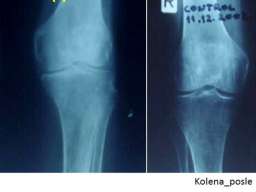

• posebno efikasno obnavljanje hrskavice – jedinstveno u svetu.

• degenerativnih koštano-zglobnih oboljenja i povreda (obnavljanje međuzglobnog prostora kičmenih pršljenova; obnavljanje zglobnog prostora kuka; obnavljanje zglobnog prostora kolena; zarastanje komplikovanog preloma pršljena; zarastanje preloma drugih kostiju; obnavljanje potpornog tkiva zubâ u slučajevima paradontopatije);